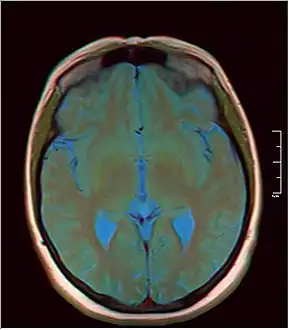

MRI axial in false color